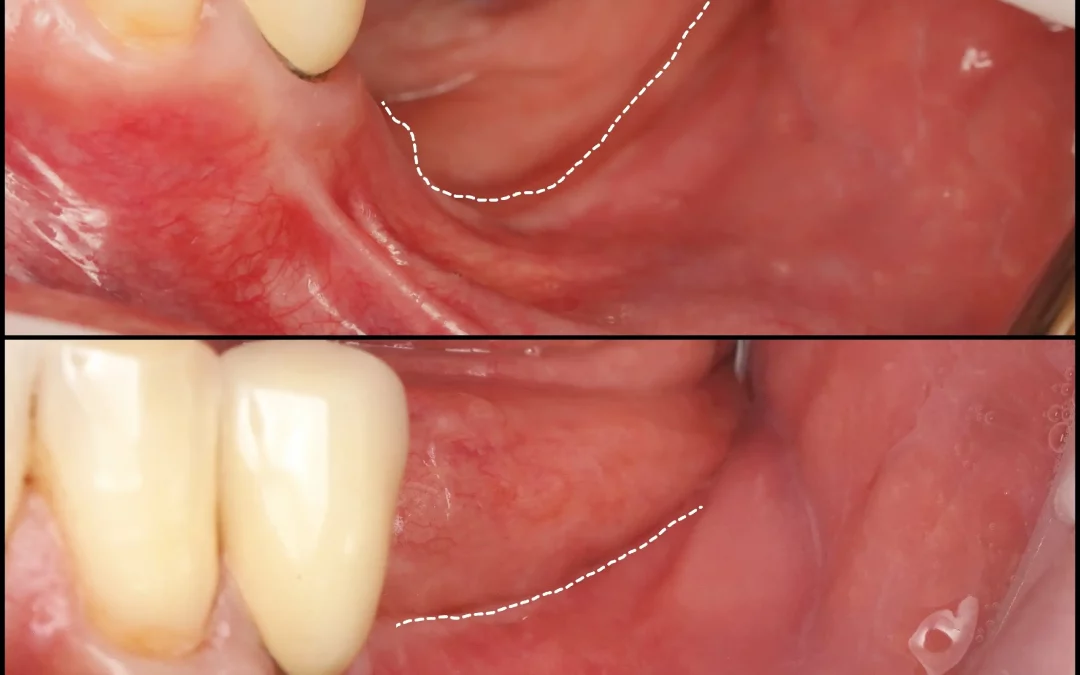

Татьяна Ковалева | Клинический кейс TK-73

Отсроченная имплантация в области зуба 4.6, работа с мягкими тканями Проведено: 1. Имплантация MIS C1 в области 4.6 зуба, ФДМ, пластика десны с обеих сторон альвеолярного гребня (СТТ из бугра). 2. Через 5...